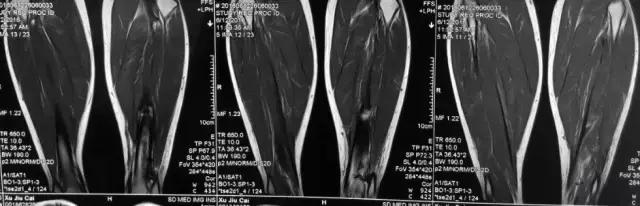

影像检查

诊断:感染。 检查:膝关节MRI,确认伤口窦道是否与髓腔相通。 治疗:1、血沉和C反应蛋白正常,目前无需特殊处理。 2、如果窦道反复出现或血沉和C反应蛋白升高可考虑手术。如证明窦道与髓腔相通,需行扩髓。

核磁示中下段骨髓炎,上面切口处流脓,请问张主任你的意见要上手术吗?

北京积水潭医院张伯松:

1、是具备手术指征了!也就是说可以手术。 2、并不是必须马上手术。不发热,不红肿、化验都正常也可以换药口服抗生素。